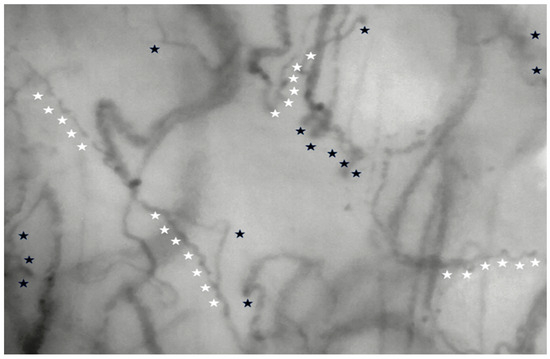

2.2. Patients and Measurements

- Chalkias, A.; Papagiannakis, N.; Katsifa, K.; Destounis, A.; Gravos, A.; Kanakaki, S.; Karapiperis, G.; Koufaki, F.; Prekates, A.; Tselioti, P. Characterization of Sublingual Microvascular Tortuosity in Steady-State Physiology and Septic Shock. Biomedicines 2025, 13, 691. [Google Scholar] [CrossRef] [PubMed]

- Ince, C.; Boerma, E.C.; Cecconi, M.; De Backer, D.; Shapiro, N.I.; Duranteau, J.; Pinsky, M.R.; Artigas, A.; Teboul, J.L.; Reiss, I.K.M.; et al. Second consensus on the assessment of sublingual microcirculation in critically ill patients: Results from a task force of the European Society of Intensive Care Medicine. Intensive Care Med. 2018, 44, 281–299. [Google Scholar]